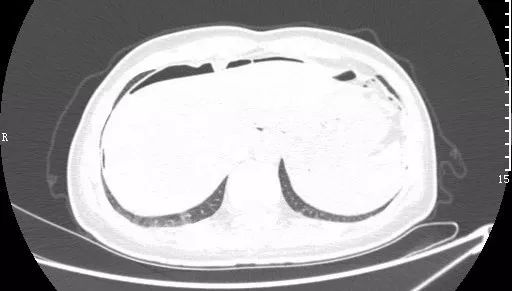

急性坏死型胰腺炎:CT平扫,胰腺密度不均匀减低,胰腺边界模糊,胰腺周围较多渗出积液,肝周可见积液。